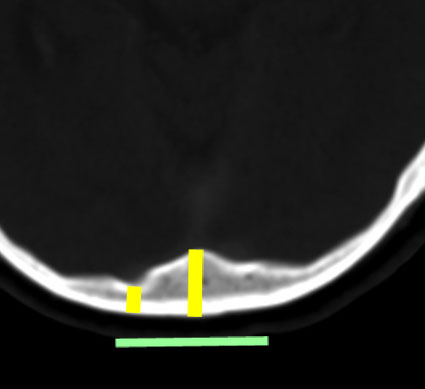

ビデオに見せているように下方から除いて横にドリルを動かしながら削除するのが効率的です。正中は内後頭隆起のためにとても深く厚い骨削除(黄色の線)となります。しかし,左右外側方向は後頭葉後頭極がありますので頭蓋骨が相対的に薄く硬膜がすぐにでます。両側の後頭極硬膜を確認しておいてから,内後頭隆起の深い骨稜を削除することが安全です。後頭極を覆う頭蓋骨の厚さには個人差があり,とても薄い骨の人がいますので気をつけます。緑の線の幅くらいを横に広く開けます。

静脈洞交会に入る前の矢状洞にはさまざまな形態があります。左の画像は二股に分かれて,左右の横静脈洞が繋がる福路があります。この要な時には左右どちら側の開頭を行っても同じです。